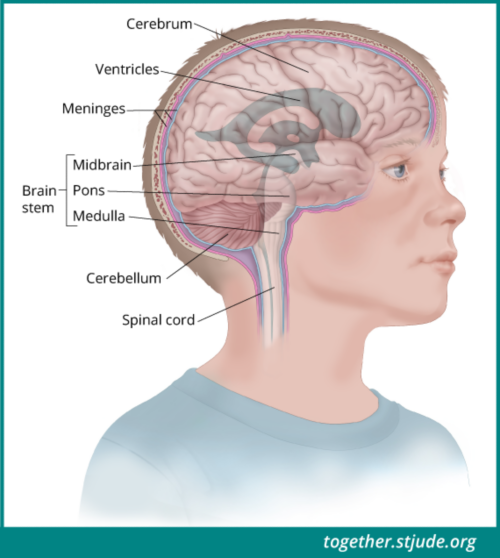

Search q draw e0 a4 ae e0 a4 be e0 a4 a8 e0 a4 b5 e0 a4 ae e0 a4 b8 e0 a5 8d e0 a4 a4 e0 a4 bf e0 a4 b7 e0 a5 8d e0 a4 95 e0 a4 95 e0 a4 be e0 a4 a8 e0 a4 be e0 a4 ae e0 a4 be e0 a4 82 e0 a4 95 e0 a4 bf e0 a4 a4 e0 a4 9a e0 a4 bf e0 a4 a4 e0 a5 8d e0 a4 b0 e0 a4 b9 e0 a4 bf e0 a4 82 e0 a4 a6 e0 a5 80 tbm isch (फाइल का प्रकार jpg)